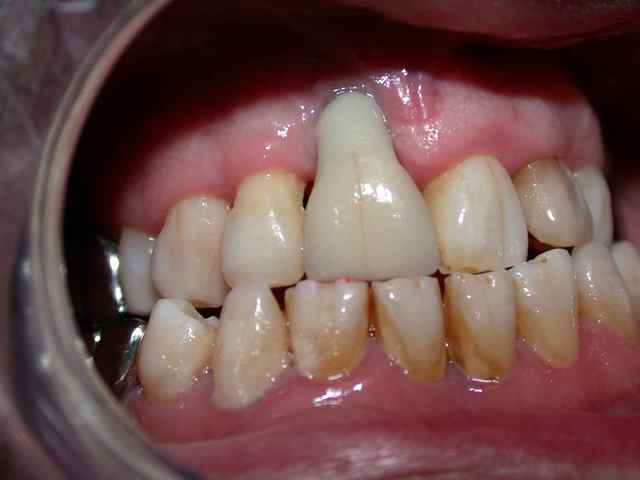

début en 2001 : patient avec perte de 32 me demande de remplacer dent manquante réponse ok avec pano et rvg pas de scan vu la hauteur visible et en pus on est en 32 .

le jour de la pose : j'avais prévu un 12*3.3 je le mets en place mais tourne à15 newton donc poubelle et je mets en pace 4*12 blocage à 30 newton mais sensation particukière au forage

puis attente et au deserrage de la vis je dévisse sans effort ce 4*12 la nje fait 1 scan qui confirme qu'iln'y a rien dans le "sandwich" bicortical qui est bien présent donc endo de 33 depose en deserrant la vis de l'implant sans effort curetage ++++ pas de prf et perlimpinpin attente de cicat 6 mois

et repose d'1 3.3*12 (on en est à 3 futs) attente bonne sensation au forage et attente avec atelle collée toujours puis 6 mois après en serrant le fm

à 30 le patient me dit "il y à qqchose de sensible" je mets la provisoire quand même qui est restée en place 1 an et demi mais je l'ai déposé (mobilité +++) et ai réalisé une prothèse "conventionelle"